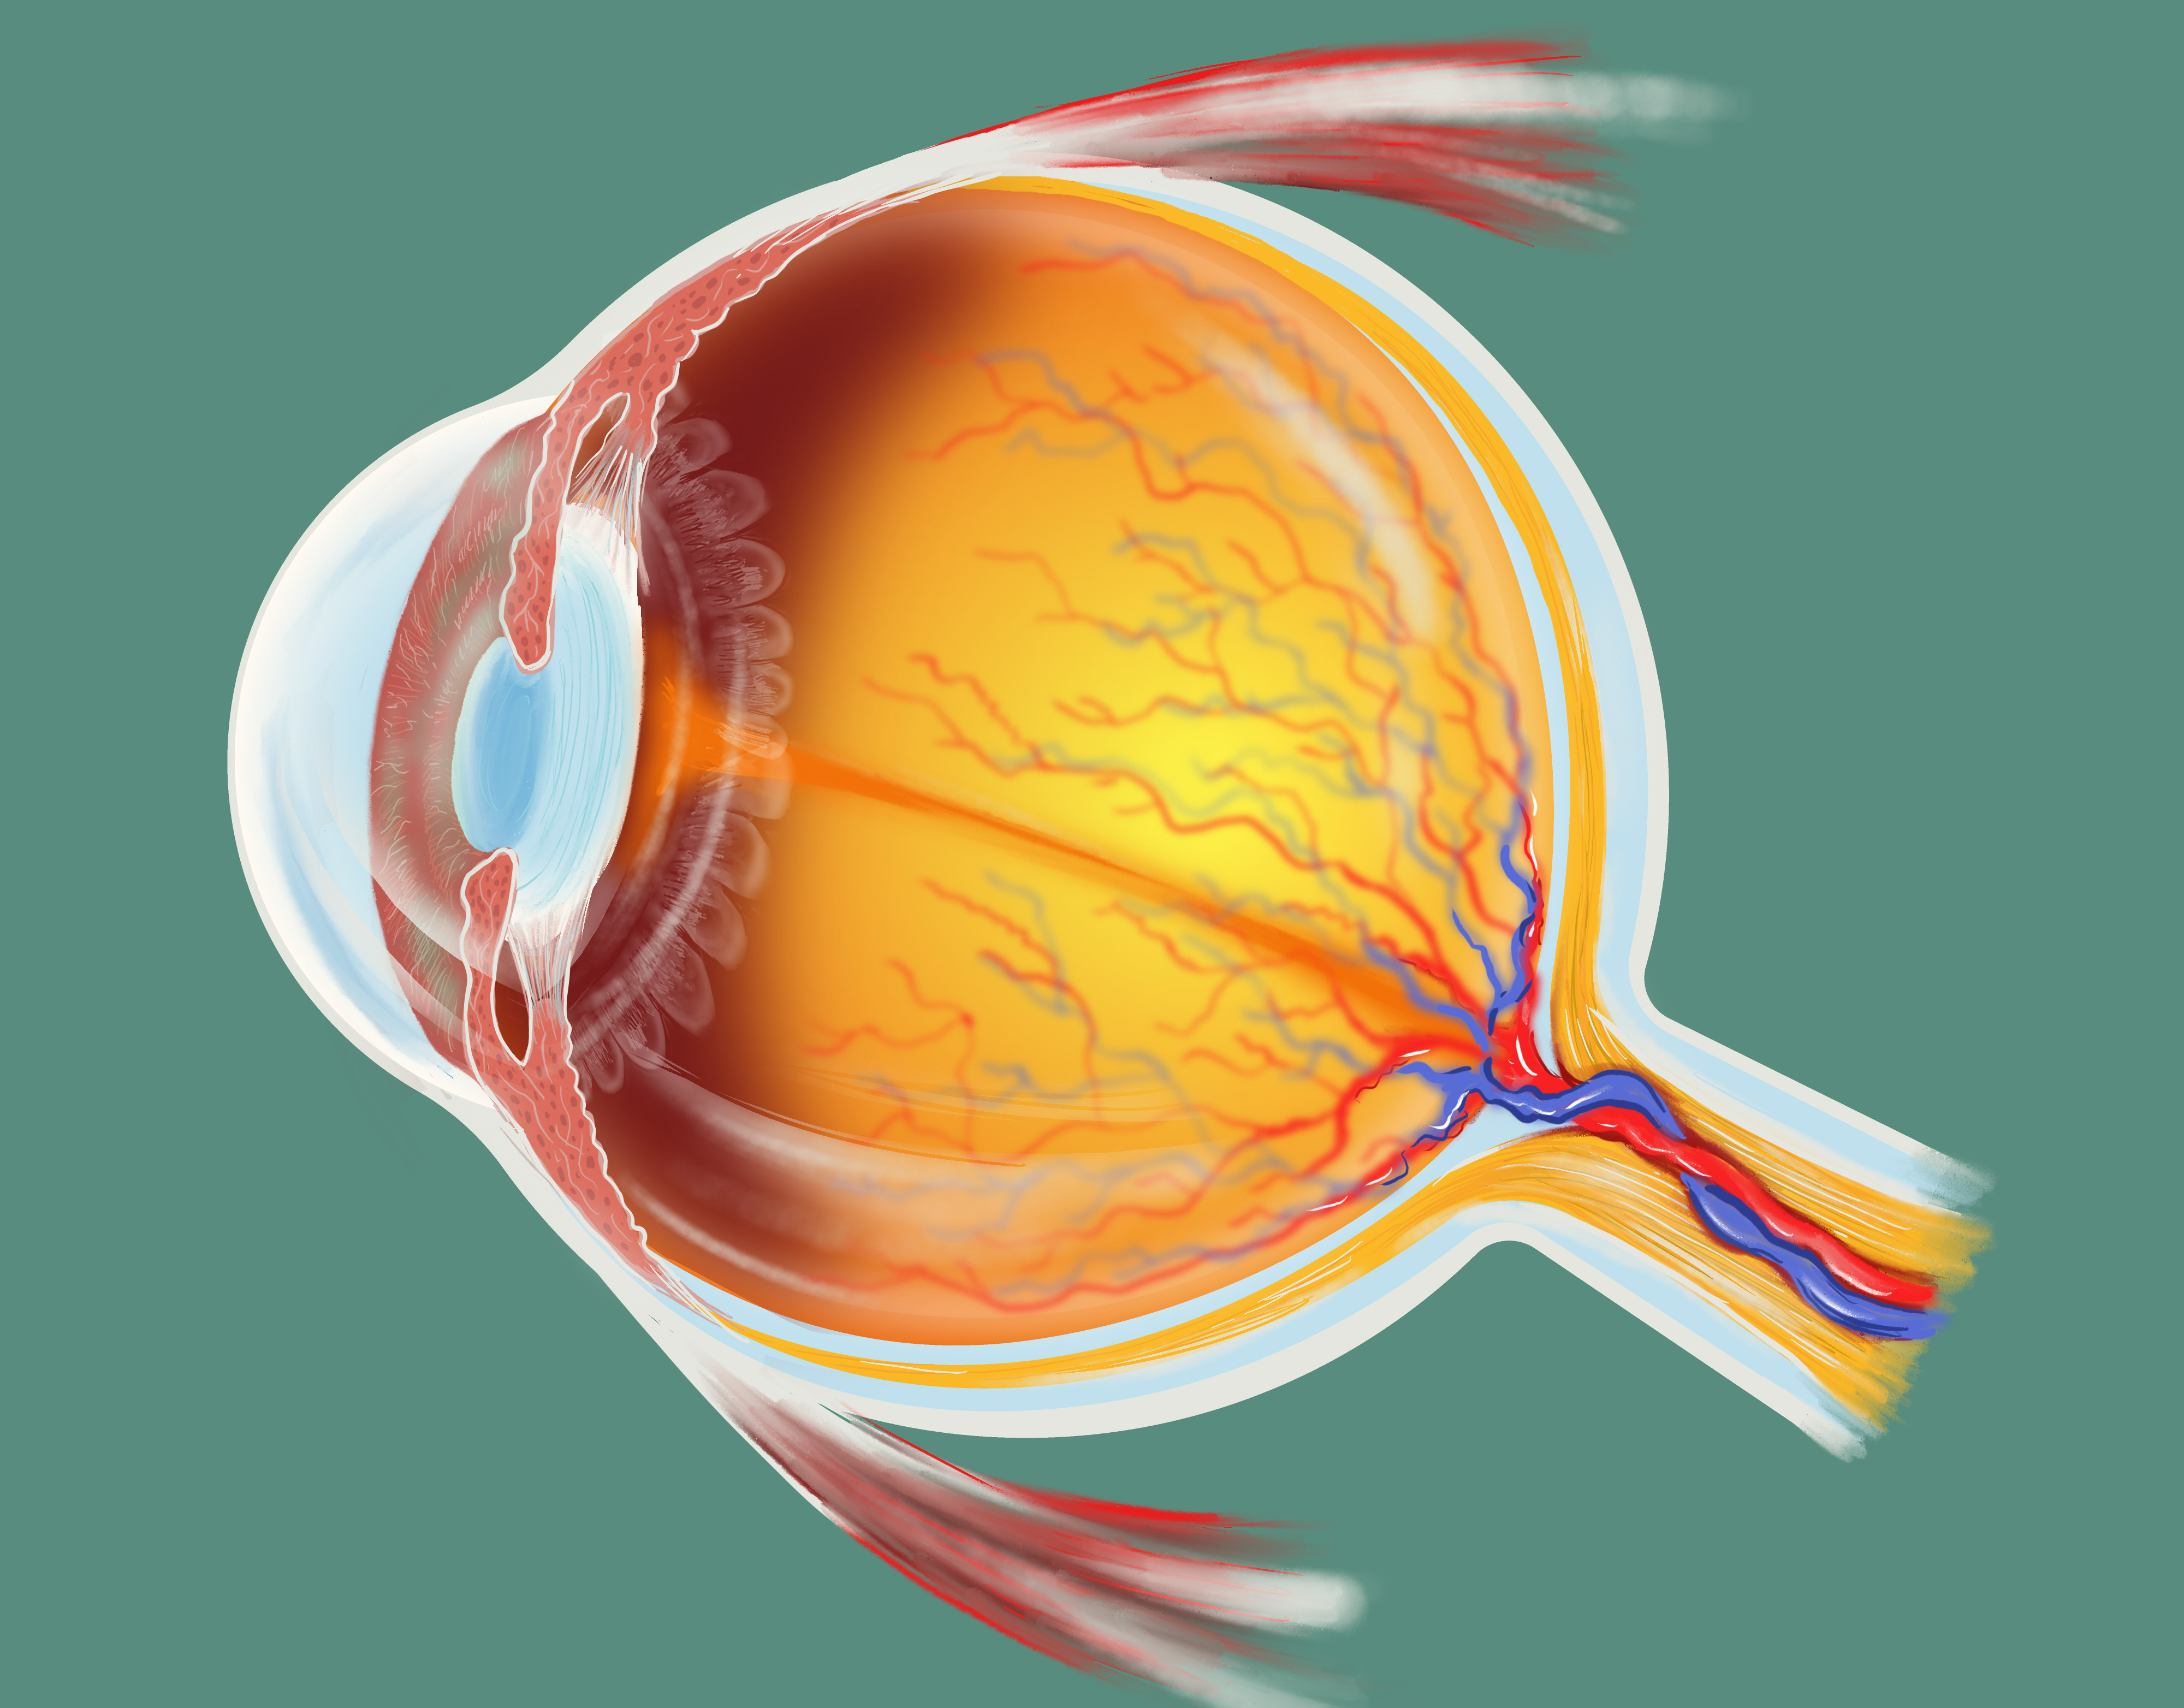

Anatomía ocular